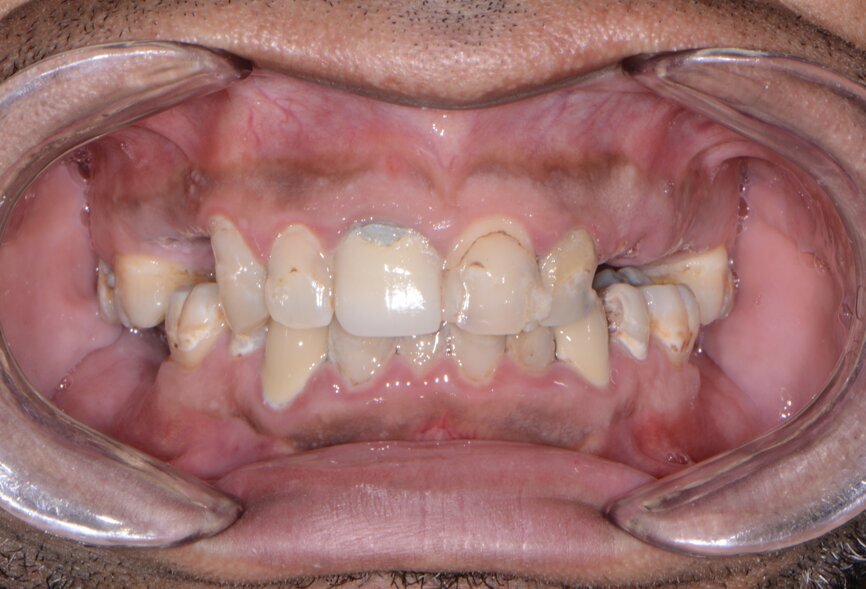

A patient presented to my practice for a consultation wanting to restore his dentition to proper form and function (Fig. 1). He complained of generalised discomfort due to the gross caries and periodontal disease that was readily apparent (Figs. 2 & 3). There were several teeth in both arches that had so much extensive decay that only the root tips were apparent upon clinical examination. Also, there was hyper-eruption in certain areas of his posterior dentition, as well as a deep impinging bite in the anterior.

Fig. 1: Pre-op retracted frontal view.

Fig. 2: Pre-op maxillary occlusal view.

Fig. 3: Pre-op mandibular occlusal view.